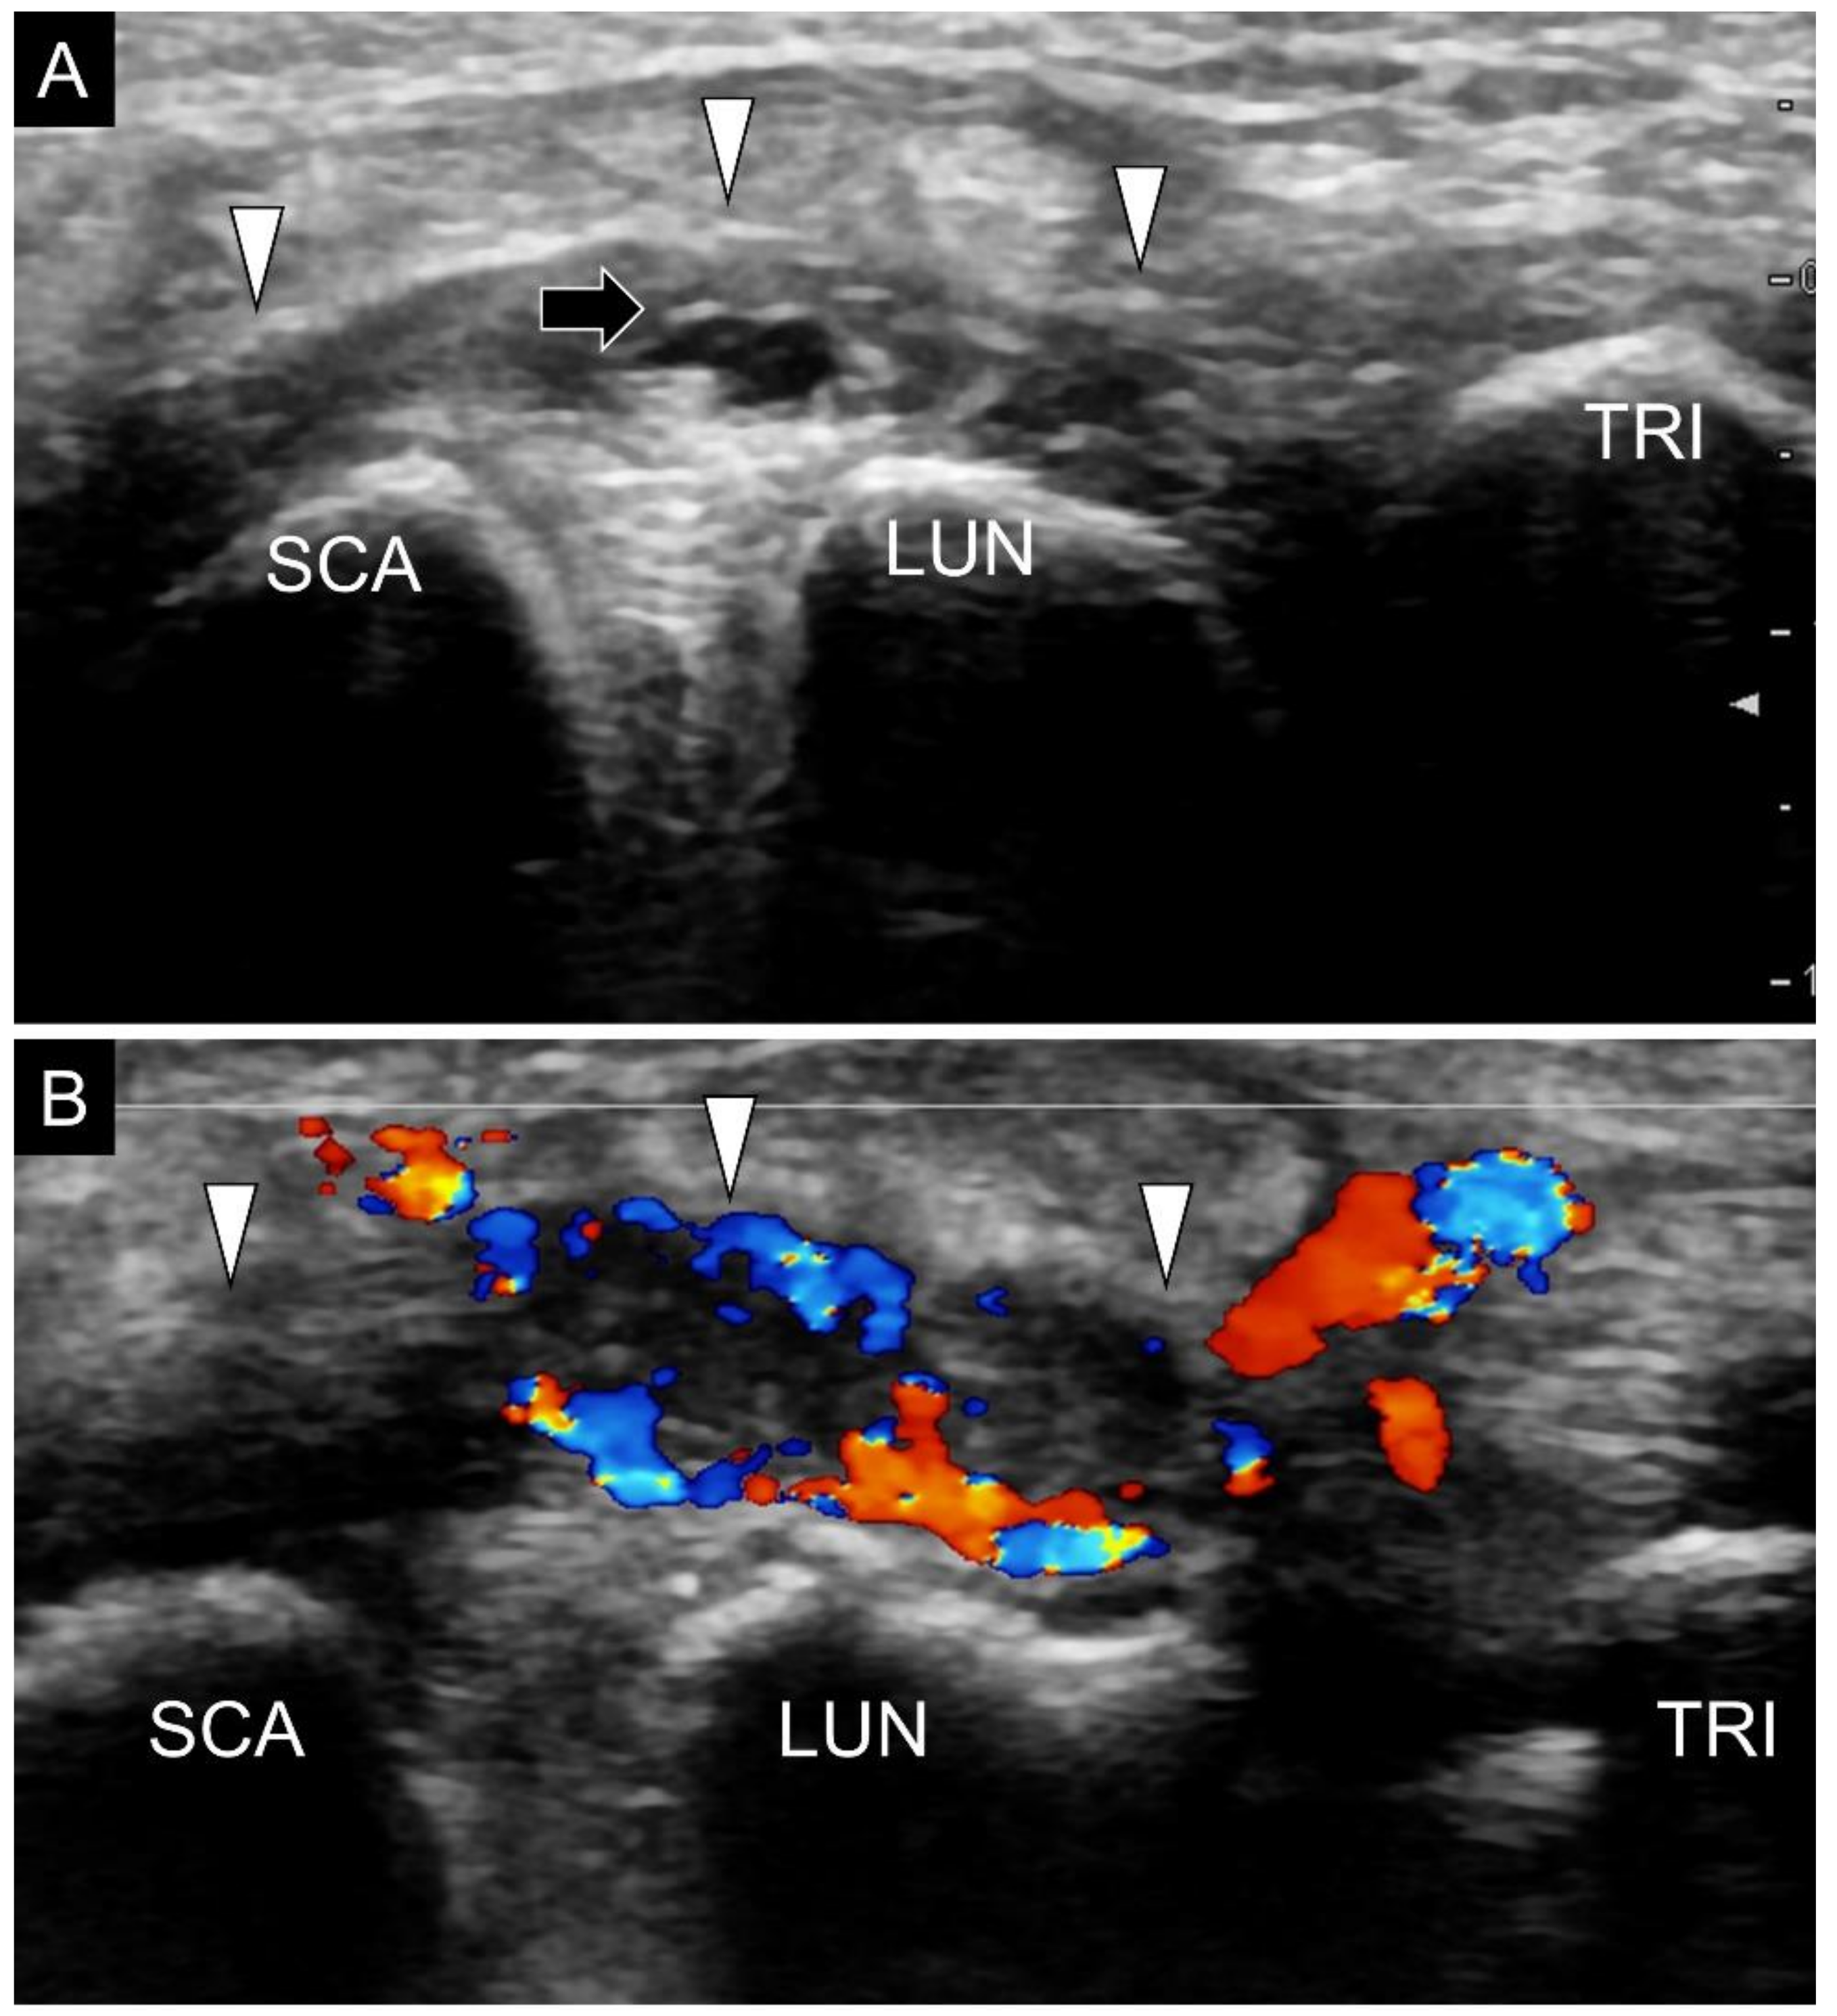

8. Pathology

4. Sonoanatomy of Volar Intrinsic Carpal Ligaments